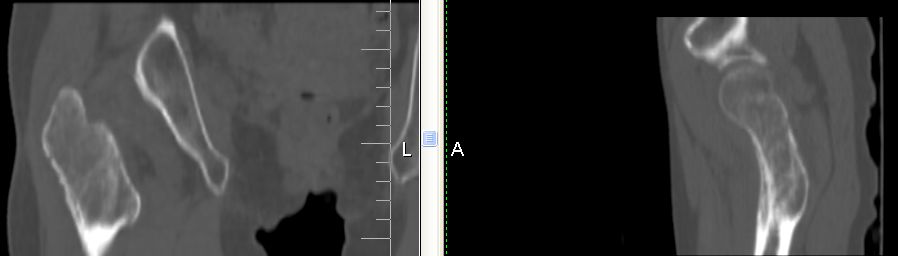

以下是引用余辉在2007-12-5 17:25:00的发言:[br]右侧股骨颈及粗隆区略显膨胀,密度增高略呈不均匀毛玻璃样改变,骨皮质毛糙,考虑1骨纤2骨髓瘤3转移瘤,建议上传软组织窗